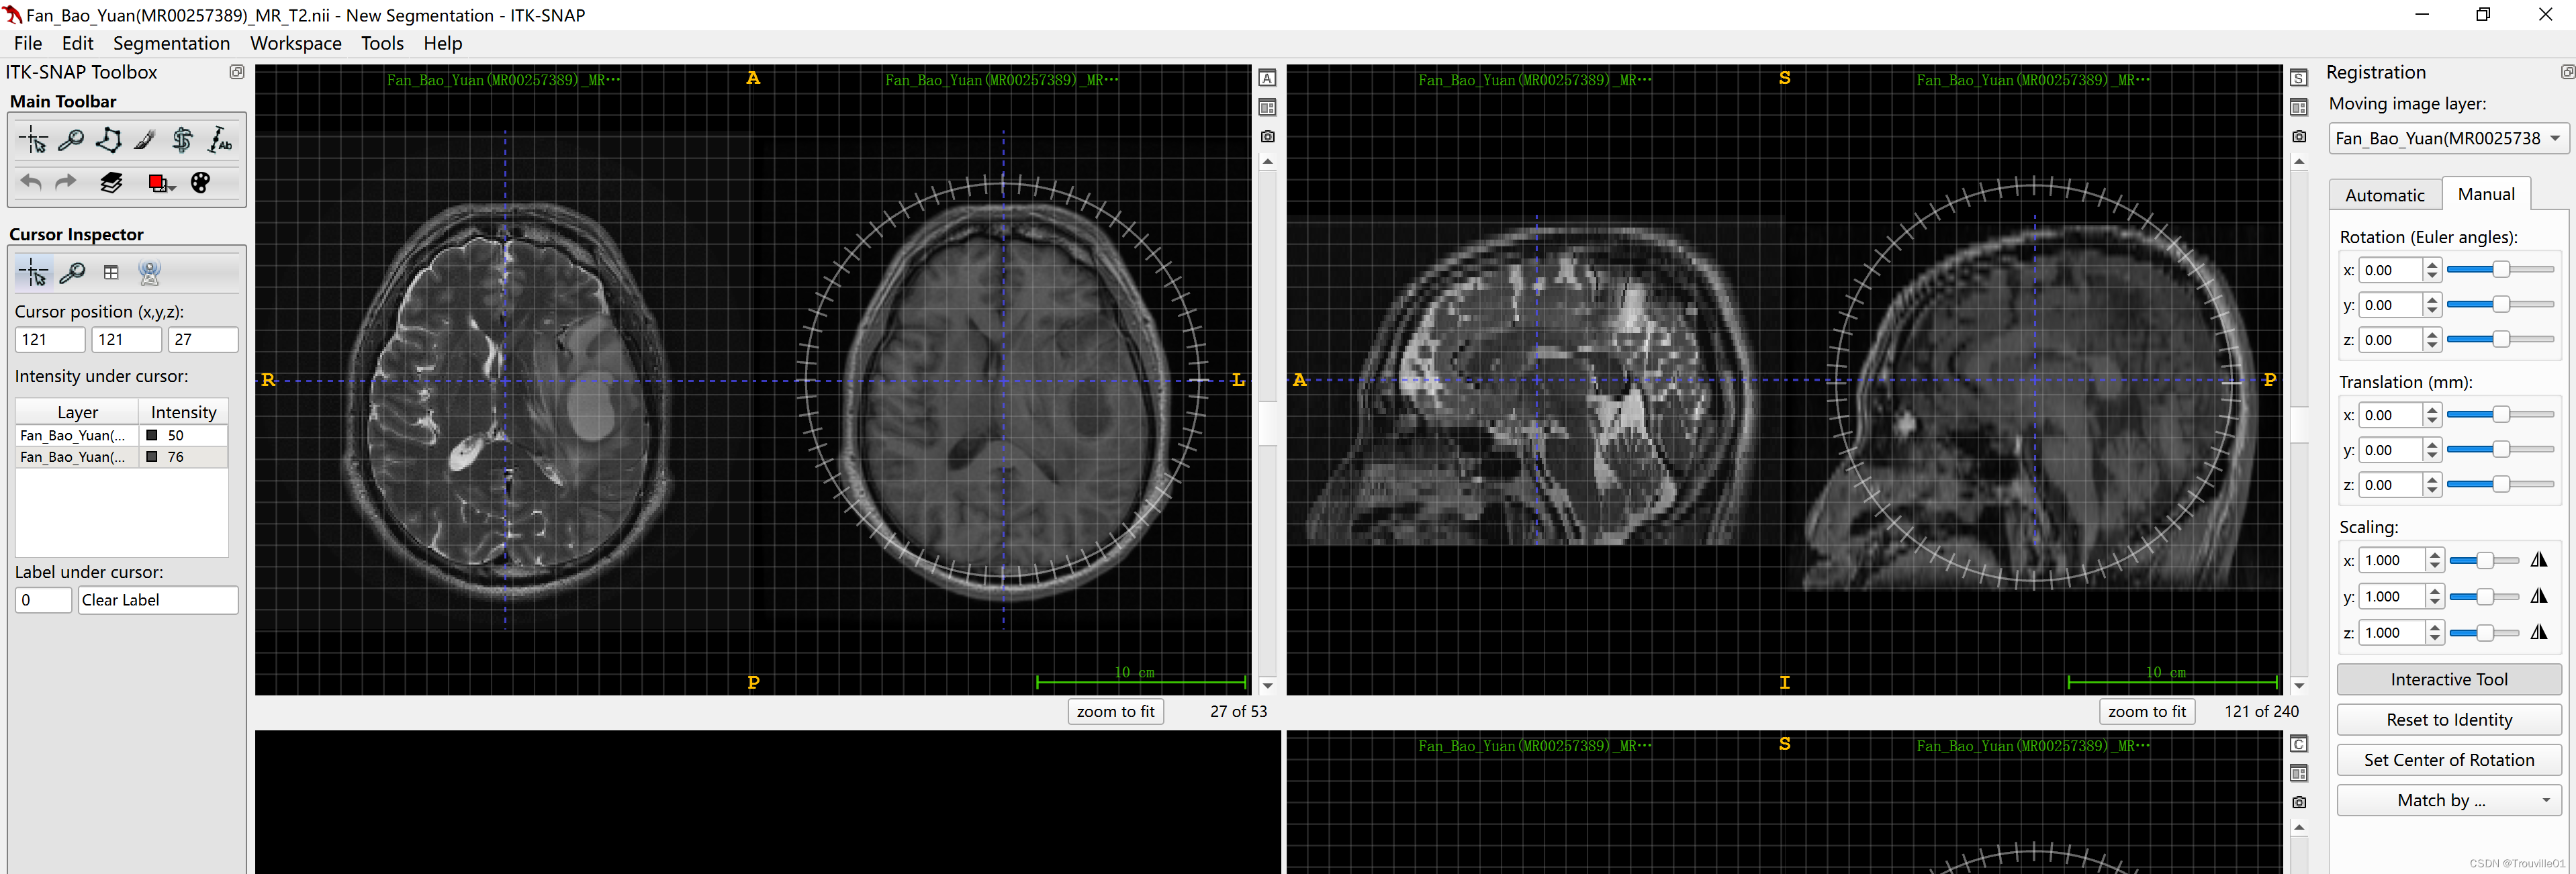

首先,确定你想要配准到的模态,比如,你想将T1W的序列配准到T2W序列上,这样可以使用T2W的标注ROI。那你需要首先打开T2W作为fix_image,然后再打开T1W作为moving_image,注意顺序不能错,如下图:

1.打开T2W

2.再拖入T1W, load as Additional image

3.单击小控件(显示提示的那个控件),改变排列方式